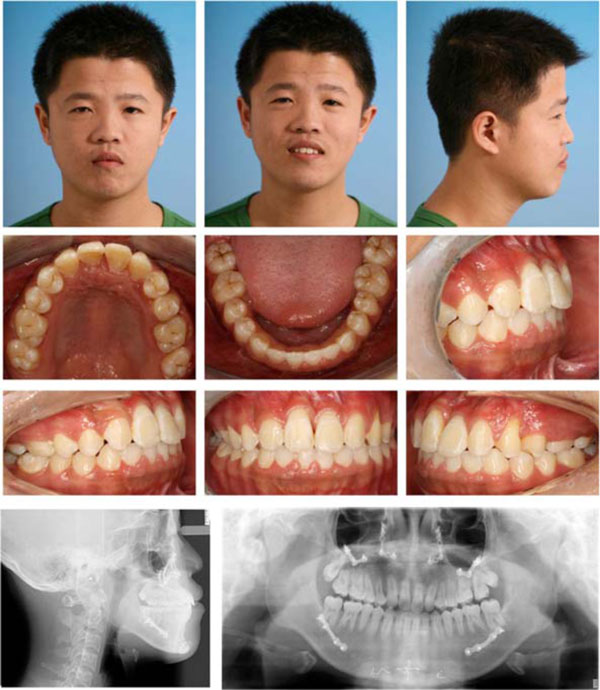

Post-treatment facial, intraoral photos and radiographs.

After combined orthodontic-surgical treatment, all treatment objectives were fully achieved including an ideal overjet and overbite with well-interdigitated class II molar relationship. The repositioned upper bilateral canines and first premolars moved mesially and took the physiological positions of lateral incisors and canines individually with slight occlusal adjustment. The incisors and canines had an acceptable gingival contour. The post-treatment radiograph revealed no periodontal bone loss, minimal root resorption, acceptable root parallelism of the newly positioned incisors and canines (Fig. 4). The cephalometric data showed that the sagital skeletal relationship was corrected from Class III to normal and the mandiblular plane was maintained (Table 1).